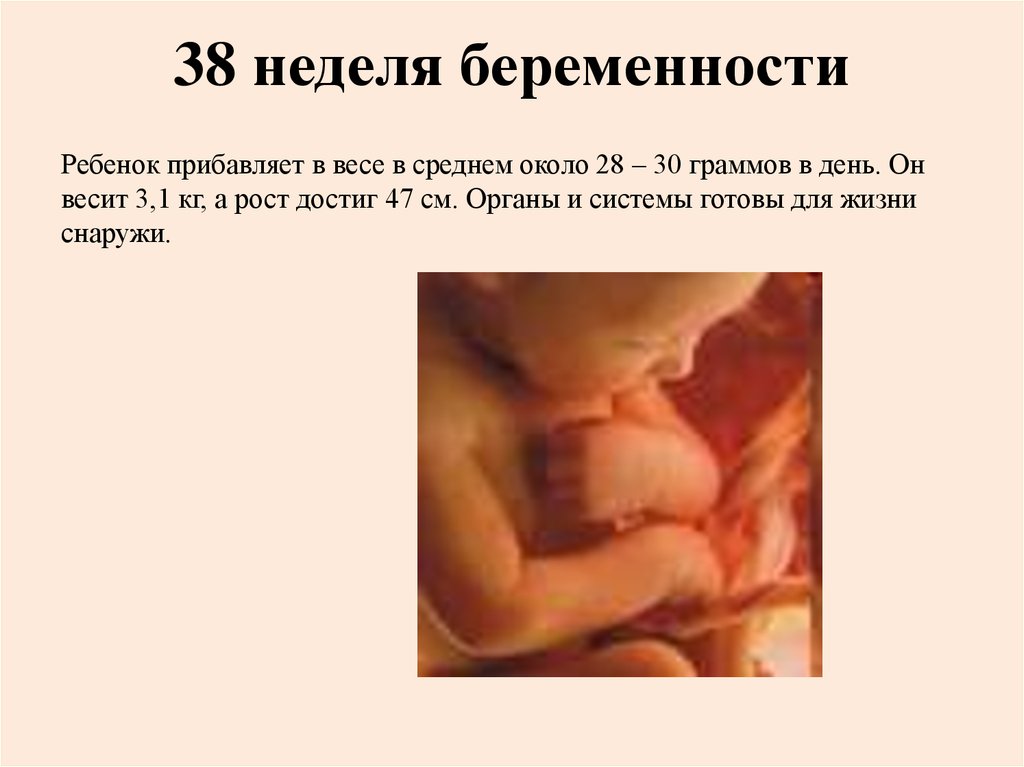

Плод 39 Недель Фото

Плод 39 Недель Фото 100 фото